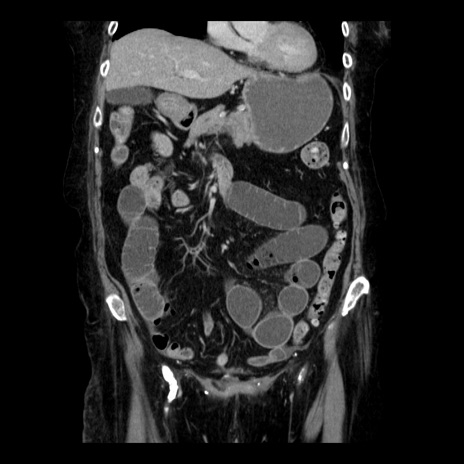

症例14(冠状断像)

【症例】 90歳代女性

【主訴】 腹痛・嘔吐

【現病歴】今朝から左側腹部痛を認めた。 経過観察していたが、嘔吐を認めたため来院。

【既往歴】 子宮癌術後

【身体所見】 意識清明、BP 127/54mmHg、P 98bpm Sp02 95%(RA)、BT 35.8°C、腹部平坦・軟腸ぜん動音聴取良好、右下腹部圧痛(+) 反跳痛なし

【データ】WBC 9800、CRP 0.46